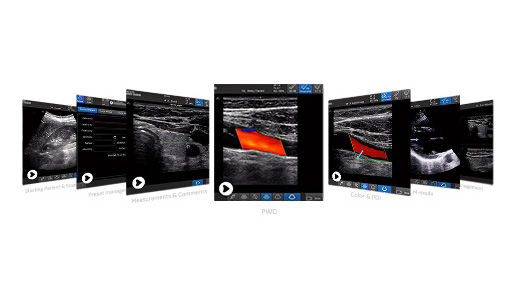

Product tutorial gallery

Get a first-hand look at how Venue supports practitioners in intensive care or critical care units.